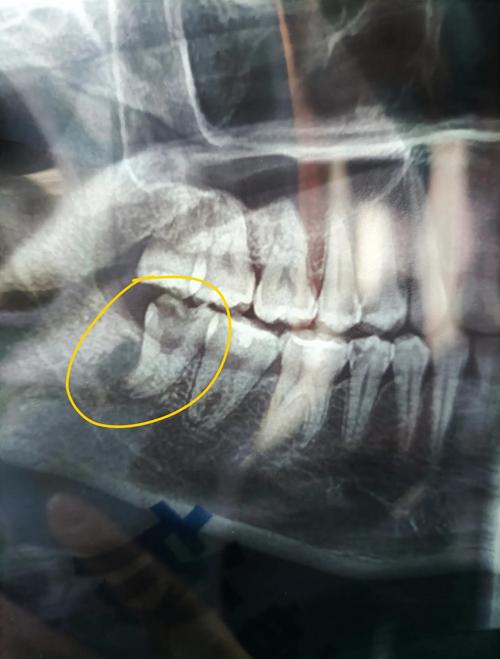

早期牙根吸收通常无明显自觉症状,多在矫治结束后通过影像学检查发现,随着吸收进展,患者可能出现牙齿松动度增加、咬合不适,甚至牙冠变色(涉及牙髓时),诊断主要依赖X线片:曲面断层片可观察全口牙根吸收情况,根尖片能清晰显示牙根表面吸收陷坑的深度与范围,锥形束CT(CBCT)则可三维评估吸收程度及对牙周组织的影响,临床上常按照Hausamen分级法将吸收分为四级:Ⅰ级(吸收<牙根长度1/4)、Ⅱ级(1/4≤吸收<1/2)、Ⅲ级(1/2≤吸收<2/3)、Ⅳ级(吸收≥2/3),级及以上被视为重度吸收,需积极干预。

证据是诉讼的基础,患者需准备:①病历资料(正畸前检查记录、知情同意书、治疗过程记录);②影像学资料(治疗前后的X线片、CBCT,用于对比吸收进展);③损害后果证明(牙齿松动度检测、咬合功能评估、后续治疗费用票据);④鉴定意见(司法鉴定报告),若医疗机构存在篡改病历、隐匿证据等行为,法院可推定其承担不利后果。

A:主要通过以下证据证明:①治疗前后的影像学对比(如治疗前X线片显示牙根完好,治疗后出现吸收);②专业鉴定意见(鉴定机构通过排除遗传性疾病、牙周炎、外伤等因素,认定吸收与正畸力相关);③病历记录(若治疗前医生未进行必要的牙根形态检查,或未告知患者个体风险,可视为过错),若多名患者在同一机构接受正畸治疗后出现类似吸收,也可作为间接证据。